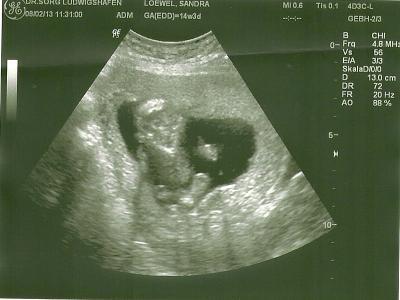

Ich war heute beim meiner FÄ und Neo war so knuffig, hat Grimasen gemacht, gewunken und auf dem einen US Bild sieht es aus als wenn er den Daumen hoch machen würde. Zwischendurch hatte er Schluckauf und hat sich dann demonstrativ mit dem Rücken zu uns schlafen gelegt. Heute bei 14+3 ist er 8,5 cm groß und wiegt 103 g. Alles zu der Zufriedenheit meiner Ärztin und ich habe auch 300g zugenohmen. In knapp 1 1/2 Wochen KH und 2 Wochen danach wieder zu ihr. LG

Bild zu Mein süßer Fratz - Forum für August - Mamis